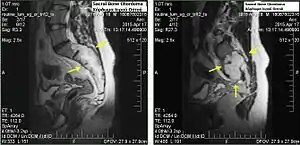

Chordomas can arise from bone in the skull base and anywhere along the spine. The two most common locations are cranially at the clivus and in the sacrum at the bottom of the spine.[2]

Sacral chordoma is presented with chronic low back pain.[3]

Sacral chordomas make up 2 to 4% of all primary bone tumours and 44% of all primary sacral tumours, thus making it the most common malignant sacral tumour. About 50 to 60% of chordomas are located in the sacrococcygeal region. Males aged between 40 and 50 years are twice as more common than women to get sacral chordoma.[3]